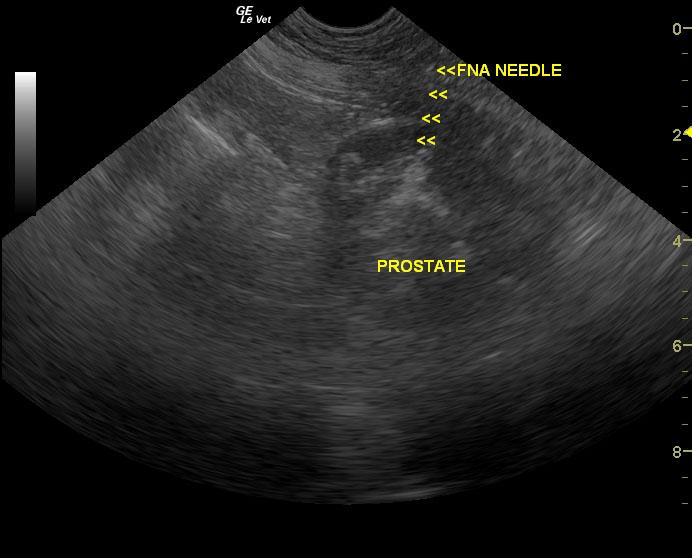

A 14-year-old MN Labrador Retriever was presented for evaluation of pollakiuria and hematuria. The patient had been on Deramaxx for chronic arthritis.

A 14-year-old MN Labrador Retriever was presented for evaluation of pollakiuria and hematuria. The patient had been on Deramaxx for chronic arthritis.